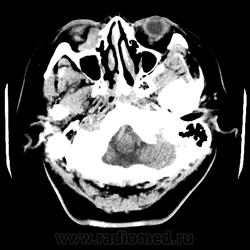

Женщина 48 лет, поступила с подозрением не ОНМК. На КТ -данных за ОНМК не обнаружено, но в правой орбите ретробульбарно мягкотканное образование +45HU, признаков деструкции и ремоделирования костных структур орбиты не наблюдается, медиальная и нижняя прямая мышца отчетливо не дифференцируются, зрительный нерв тесно прилежит к данному образованию. После КУ гомогенное накопление КВ и повышение плотности до +65HU. Экзофтальм. Жалобы на снижение зрения. Год назад делала МРТ ГМ, на снимке патологии орбит не увидел. Идиопатическая псевдоопухоль орбиты?

В мягких тканях носогубного треугольника справа тоже образование.

Натив

Контраст

На первое место все же поставила бы гемангиому. Локализация, возраст, пол, флеболит, случайная находка, безболезненный экзофтальм, ремоделирование стенок орбиты -это за гемангиому.

Кавернозная гемангиома? Ремоделирования стенок орбиты как раз таки нет, они интактны. Должна быть псевдокапсула, а здесь больше похоже на инфильтрацию прямых мышц, я за псевдоопухоль.